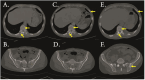

Although bone destruction and hypercalcemia without acute peripheral blast BCR-ABL-positive acute lymphoblastic leukemia (ALL) have been reported in children, they are rare in adults. Herein, we describe a case of BCR-ABL positive ALL with a triploid karyotype, WT1, and CDKN2A mutations with hypercalcemia and bone destruction as the first manifestations. Complete remission (CR) was achieved by induction chemotherapy. BCR-ABL turned negative after treatment with dasatinib. However, computed tomography and whole-body bone scan showed extensive bone destruction. Additionally, bone biopsy showed leukemic infiltration. After treatment with dasatinib and VMCP, leukemia recurred with positive BCR-ABL. The T315I mutation occurred. The patient was surgically diagnosed with calculous cholecystitis and achieved CR2 by postoperative orebatinib and VP regimens. Later, the patient died due to a severe pulmonary infection. BCR-ABL-positive ALL with bone destruction is rare and difficult to control using tyrosine kinase inhibitor chemotherapy alone. Therefore, further exploration of more effective treatments is needed.